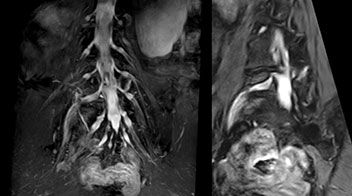

“In such case, we would then browse through axial T2-weighted MR images slice by slice and mentally reconstruct the actual situation based on both radiculography and MRI. Fortunately, NerveVIEW can now very well show nerve courses and presence of nerve compression or edema in one single image series.”

“We have often seen NerveVIEW directly depict details of the nerve compression that were not observed by radiculography. Therefore, we think that with NerveVIEW we can reduce the number of invasive examinations, especially for some patients with lumbar plexus symptoms.”

Distinguishing typical from atypical herniation informs the surgeon

“NerveVIEW is really useful for those cases where a nerve disorder is strongly suspected based on the clinical examination but our regular MRI images do not show any findings. These atypical herniations and spinal canal stenosis, occurring in 5% to 15% of the total lumbar herniation/stenosis cases are our main target when using NerveVIEW,” says Dr. Yabuki.

“Although symptoms of typical disc herniation and atypical hernia are very similar, the actual site of herniation is different. It is therefore important to characterize the nerve’s condition both inside and outside of the intervertebral foramina.

“Conversely, if we see no abnormality in NerveVIEW, we can assume at least that there is no severe condition that requires surgery. Like this, it can help us avoid unnecessary surgery. NerveVIEW can have a tremendous impact in this way.”